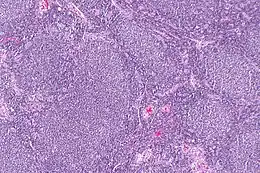

Description de l'image Follicular lymphoma -- low mag.jpg.

Lymphome folliculaire